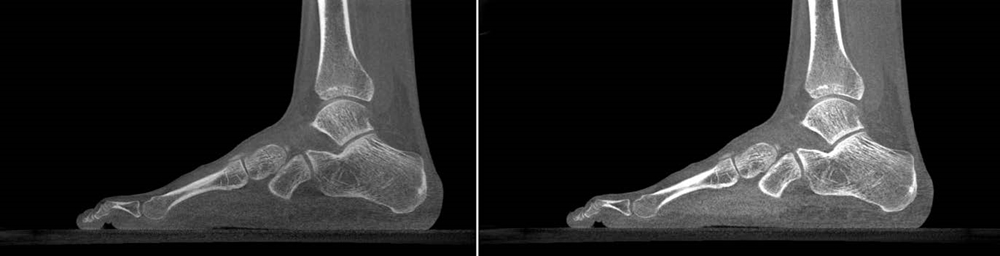

High resolution slices of a human foot in sagittal plane

IBEX Trueview® (right) increases bone contrast by 37% and tissue contrast by 53%